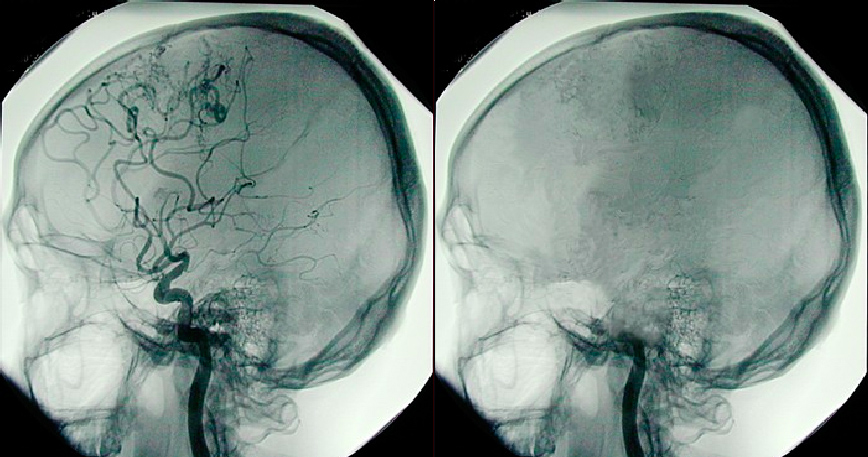

In order to complete this process, doctors will first direct the cold saline through the heart and up to the brain. This will help ensure that no permanent brain damage occurs while the rest of the body is being cooled. In order to direct the saline solution to the necessary areas, the lower region of their heart will be clamped and a catheter placed into the aorta. This catheter will direct the saline to the necessary areas. Once the most vital organs are cooled (and thus, temporarily protected), the clamp will be removed so that the saline can be pumped throughout the rest of the body. The whole process takes just 15 minutes.